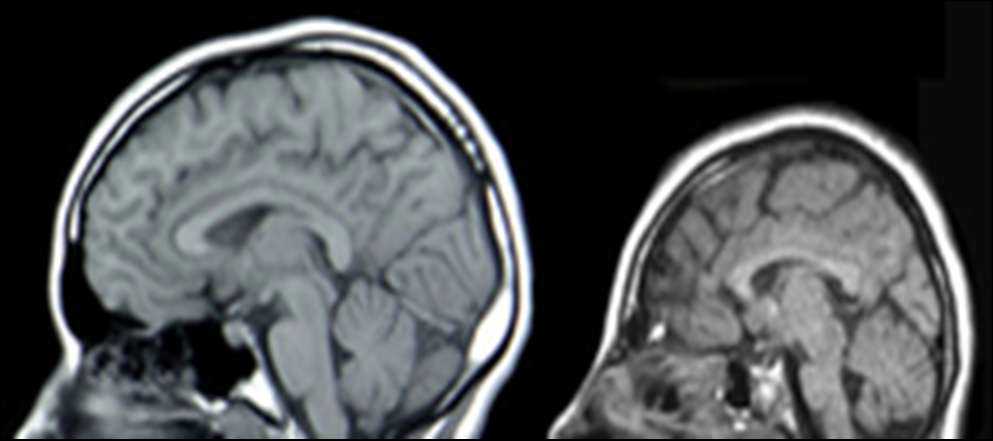

Agnese van het corpus callosum

afwijking ten gevolge van migratie